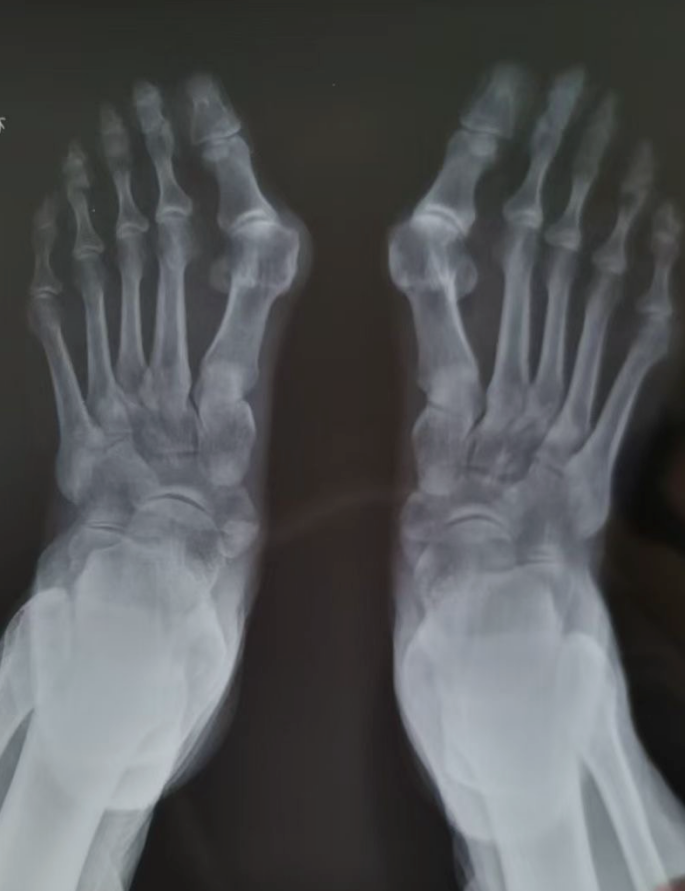

患者脚部影像资料

退休后,秦阿姨终于下定决心解决这个困扰多年的“足疾”。通过多方了解,她得知目前已有更先进的微创手术方式,于是来到武汉大学泰康临床学院、泰康同济(武汉)医院就诊。经过详细检查和评估,泰康同济(武汉)医院骨科团队为其量身定制了手术方案——采用目前较先进的微创术式,行双侧第一跖骨截骨术+骨髓内针内固定术。手术过程中,医生依次完成骨赘切除、跖骨截骨、关节复位及spear plate髓内板固定,C臂透视显示固定复位效果理想。术后检查双拇趾活动度、稳定性及关节复位情况均良好。